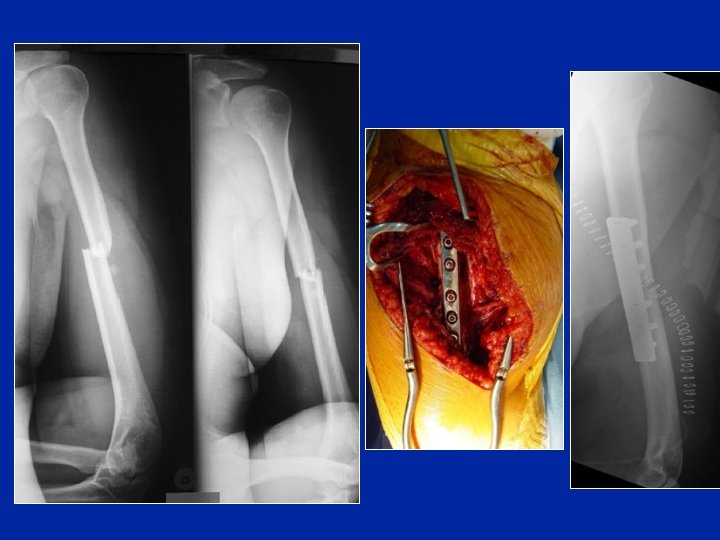

Ostéosynthèse par plaque Inconvénients : • Abord chirurgical large • Dévascularisation des fragments • Exposition du radial • Retarde la consolidation Plaque postérieure Plaque externe

Ostéosynthèse par plaque vissée : Risque de pseudarthrose ++